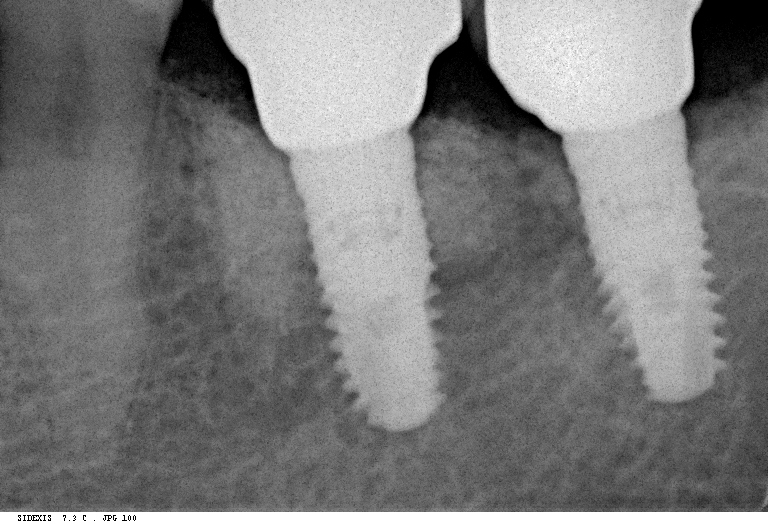

В хирургической практике я использую прицельные снимки как для первичной диагностики: например, чтобы быстро понять локализацию ретинированного зуба мудрости и его отношение к окружающим структурам, либо для интра- и послеоперационного контроля результатов имплантологического лечения. А наличие цифровой базы радиовизиографических снимков позволяет понять, как ведет себя протез на импланте в течение длительного времени:

Наиболее важным исследованием для имплантологии и хирургии является компьютерная томография. Именно с помощью нее мы досконально изучаем костную ткань в области операции, определяем ее конфигурацию и структуру, планируем размер и положение импланта в челюстной кости:

Конечно, существуют доктора, которые игнорируют важность компьютерной томографии для имплантации, но нужно помнить, что в этом случае очень высока вероятность ошибки. А в такой сфере как хирургия, ошибки не очень желательны, верно?

Я работаю со всеми существующими программами дентальных томографов. Изучение снимка, его описание и все измерения всегда провожу самостоятельно. Идеальный вариант — изначальный снимок на диске, без распечаток, измерений и описаний.